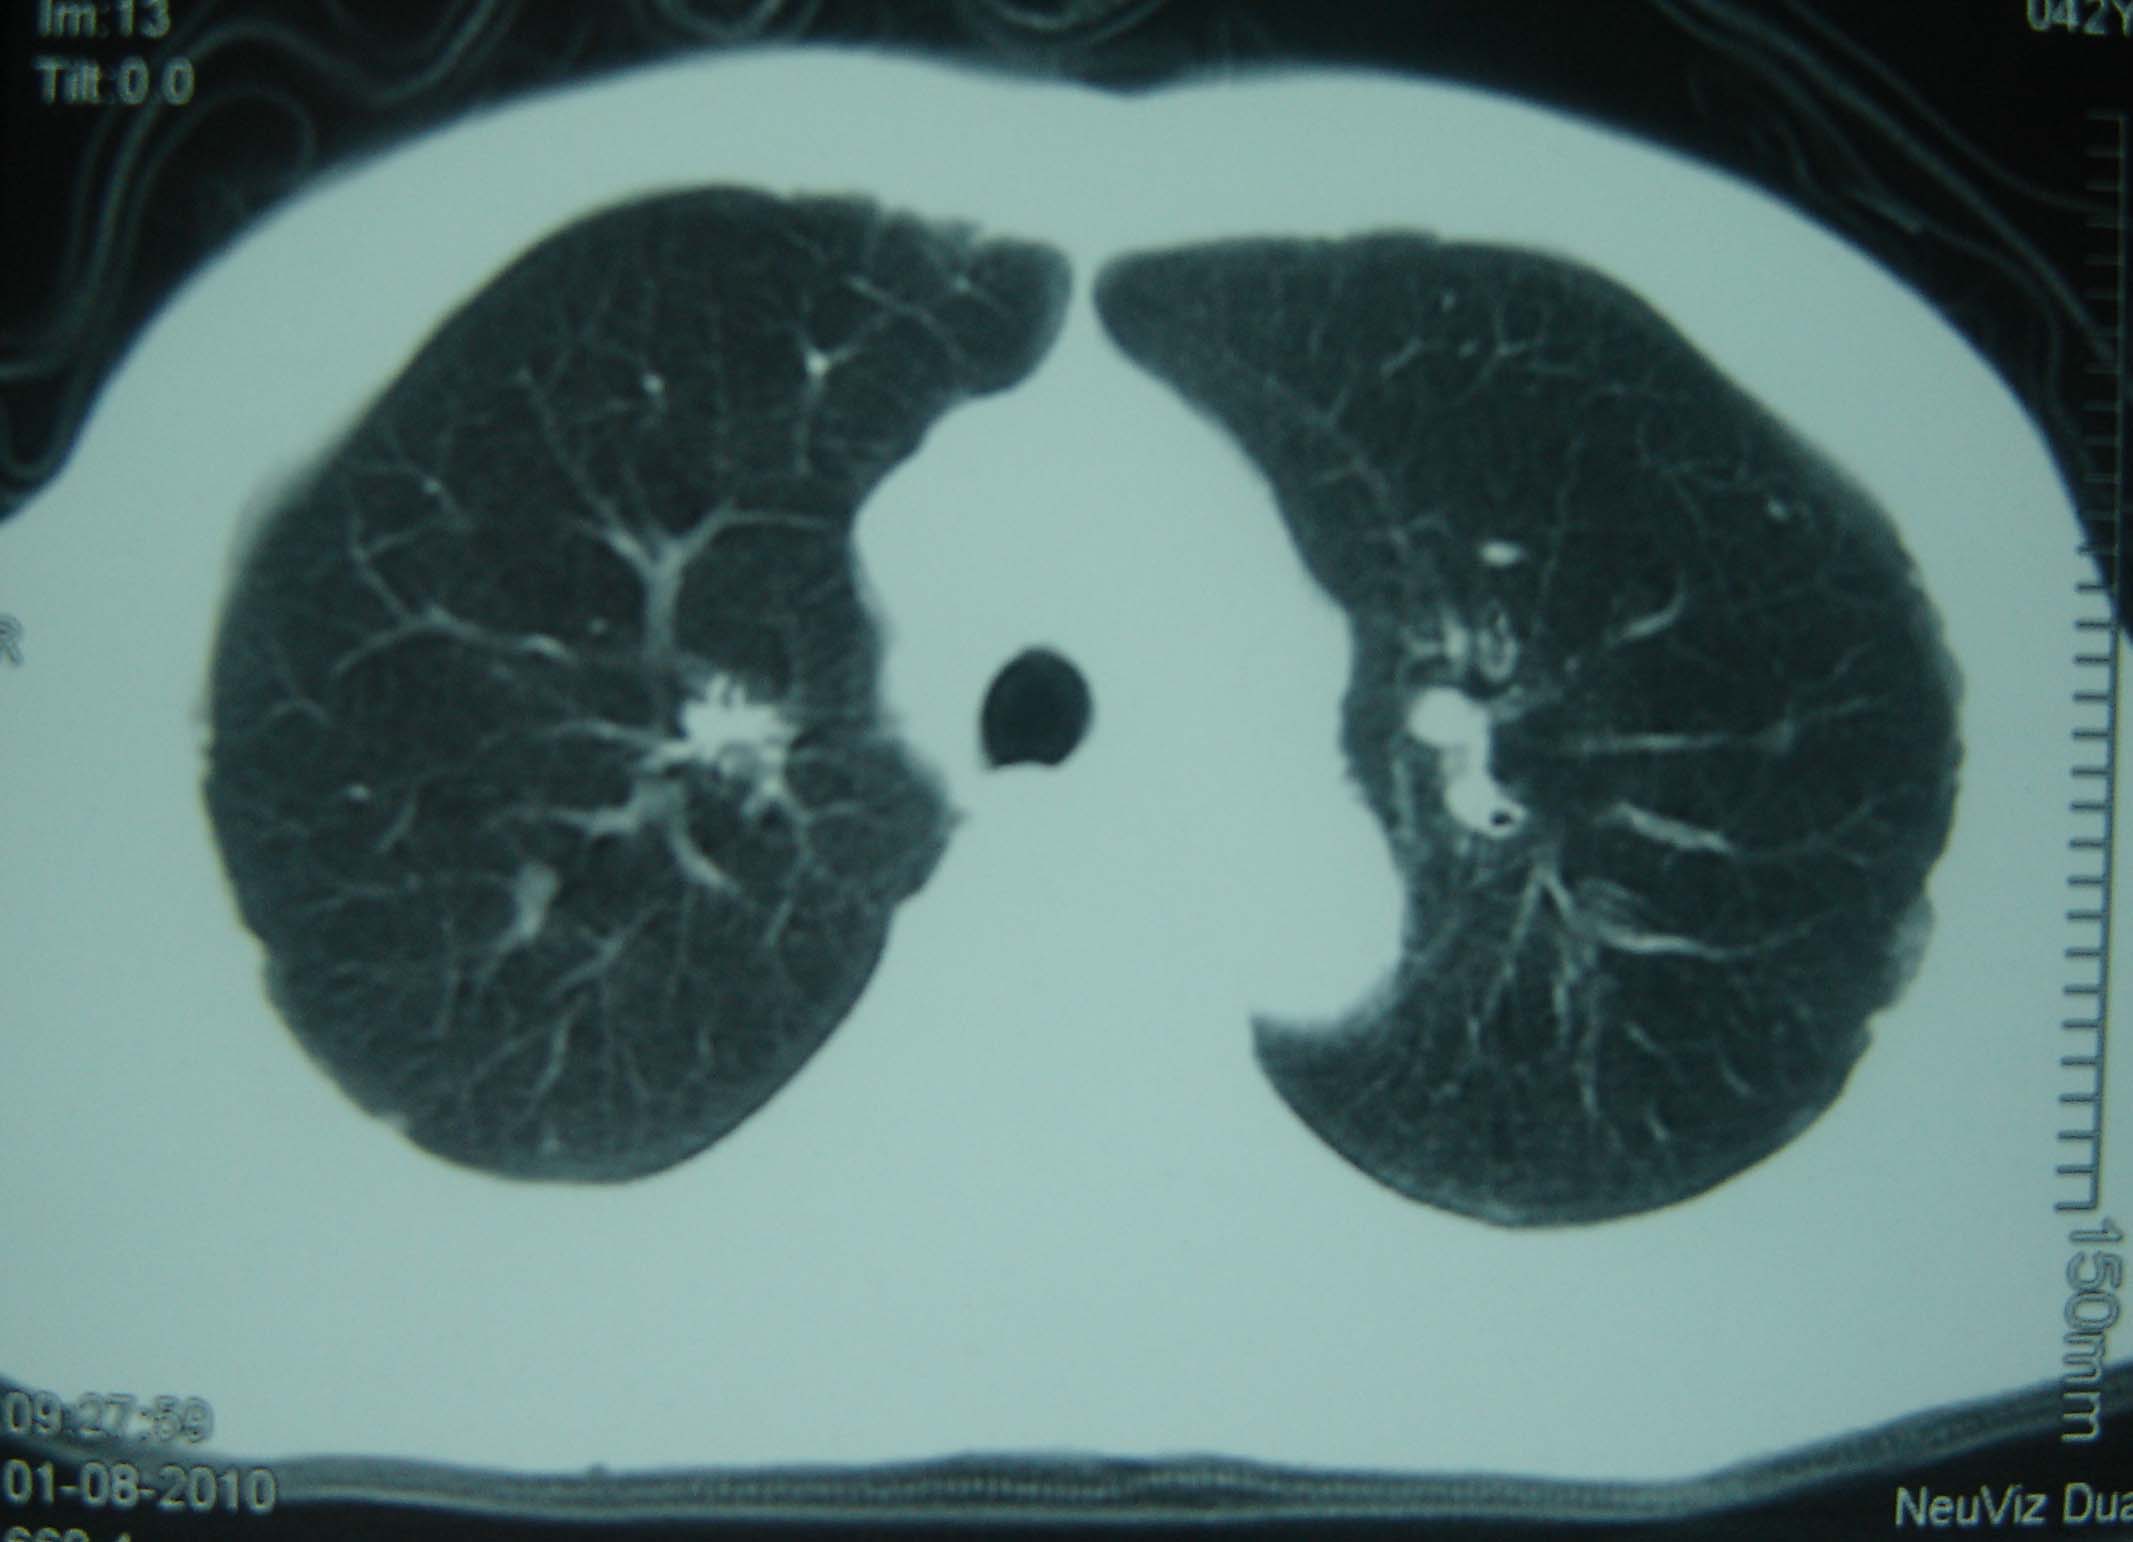

男 、43岁,咳嗽胸痛,装修工,平时接触粉尘较多,有吸烟史10多年,纤维支气管镜检查未发现异常,胃镜、腹部b超检查亦未发现异常,颈部淋巴结活检未发现肿瘤细胞。

不能排除转移,如果不能找到原发灶,只有短期随访。

结节病?转移瘤?

结节病。

转移瘤?

1)考虑双肺及胸膜多发性转移瘤。2)肺气肿。

双肺结节病。